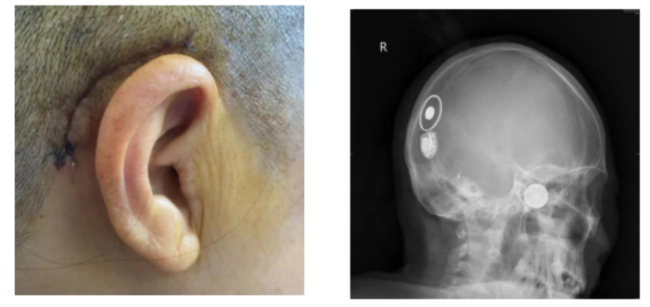

)耳鼻咽喉头颈外科专家团队为李女士进行了右侧人工耳蜗植入手术。术中,手术团队对植入的电极进行了电极阻抗测试和神经反应遥测(NRT),均提示人工耳蜗电极工作良好,电阻正常,神经反应良好,手术顺利完成。如今术后1个月过去了,植入的人工耳蜗开机调试,李女士对声音反应好,连连感谢专家团队实施手术和精心护理,让她能清晰听见这个世界的声音。

李女士接受人工耳蜗植入术后的影像图片